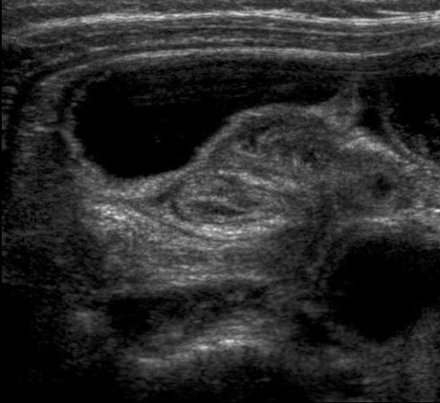

一位25岁的男性患者出现心口疼和呕吐,由于经过对症的治疗后症状没能缓解,所以来做超声检查,发现多处的小肠扩张,蠕动亢进,提示小肠梗阻。扩张和非扩张的临界点位于脐上正中,扩张肠管位于右侧(图1)。临界区的肠管没有发现内在的异常。

图1 脐上斜向扫描显示在扩张和非扩张肠管间存在过渡区(箭头)。